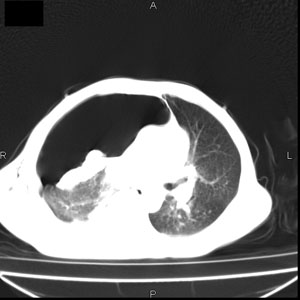

患者男,77岁,于3日前从树上摔下,头部查ct示蛛血,硬膜下出血,上腹部ct未见明显异常,右侧胸腔积液,左侧如常。肺部拍片示右侧肋骨多发骨折住院后今日来查肺部ct,我看到的是1。右侧胸腔血气胸并右肺上叶,中叶压缩性肺不张,2。右肺下叶肺挫伤并多发肋骨骨折,肌内及皮下积气3。左侧少量胸腔积液,我想请教的是3天前左侧胸腔里没有积液今天怎么出现了呢,是什么原因呢?请讨论。

有肺挫裂伤,有渗出,

回复楼主   左侧液气胸,液体来源1、肯定有血液成分,多少不一定。2、胸膜腔渗液,由于肺压缩、活动度下降,肯定胸膜吸收有问题,导致积液增多。